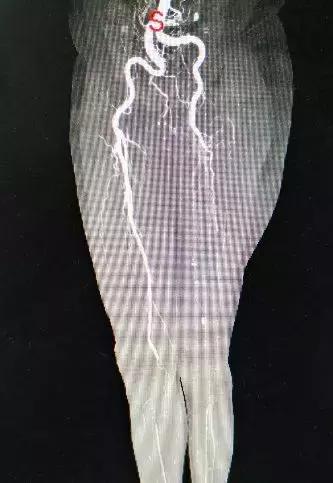

接诊的主任医师毛跃伟根据老人情况,认为应该是下肢动脉缺血引起的皮肤溃烂

仔细询问病史,结合相关影像学资料,发现鲍大爷有“房颤”,并且没有进行正规抗凝治疗,最终确定老人是房颤导致的下肢动脉栓塞并血栓形成。

结合影像,鲍大爷是下肢动脉栓塞

急性下肢动脉栓塞是指栓子(血栓)进入动脉,被血流推向血管远端,阻塞动脉血流而导致肢体缺血,以至坏死的一种病理过程

急性下肢动脉栓塞是一种急症,如果处理不当或不及时,会造成截肢或死亡的严重后果。

鲍大爷的下肢已经出现溃烂,再不及时处理,下肢有可能因长期缺血而出现坏死!

迅速确定治疗方案,为鲍大爷急诊行下肢动脉取栓手术

取栓示意图

术中顺利取出堵塞血管的栓子,完全开通血管,下肢动脉搏动恢复正常